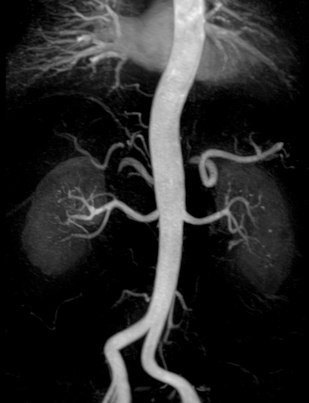

Зображення нирок з контрастним посиленням

За останнє десятиліття контрастну МР-ангіографію використовують для оцінки більшості судинних систем організму завдяки високому відношенню сигнал/шум, просторовій роздільній здатності та відносній відсутності артефактів, пов’язаних із кровотоком.